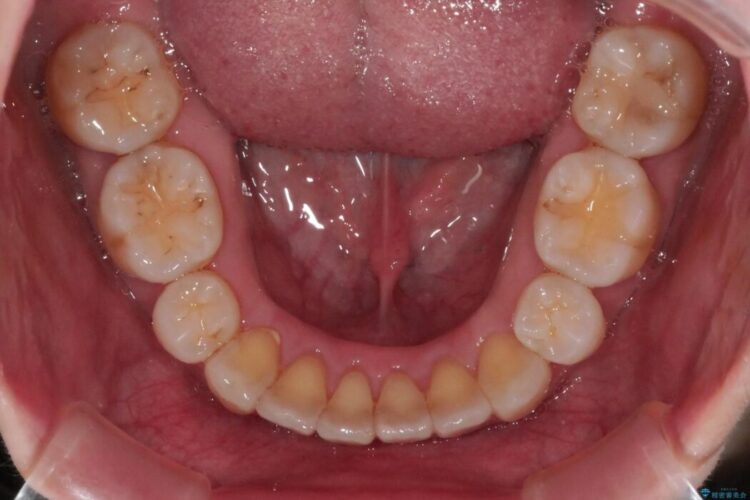

抜歯矯正後の上の前歯の後戻りが気になるとご来院された患者様です。

歯と歯の間を削るのと、歯列のU字型のアーチを僅かに外側に広げる事でスペースを作り、前歯の角度の改善をしました。